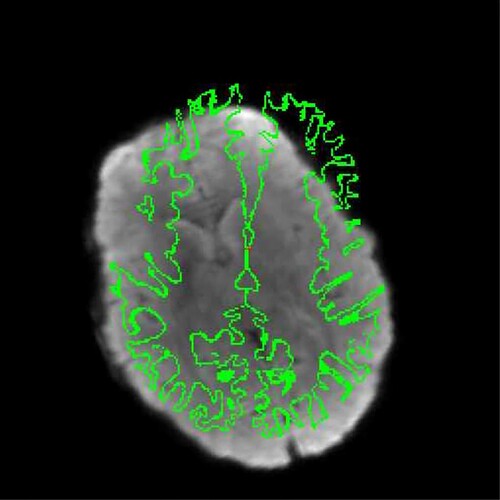

Otherwise, bbregister runs with no other errors or issues. But, the final bbregister output is terrible: